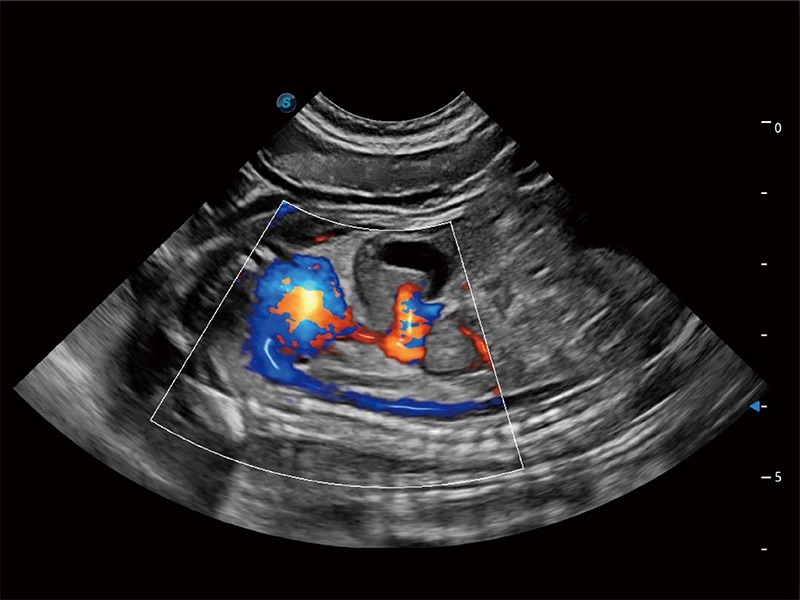

極大提升超低速微細血流的檢出能力,同時更精準地濾除軟組織和超聲信號,為獸用醫(yī)生提供以往無法通過常規(guī)血流獲得的疾病診斷信息。

在傳統(tǒng)二維血流成像的基礎上,呈現(xiàn)血流的立體感,具有動感的生命力之美。即便是微小的血管也能輕松應對,提高了血流的視覺敏感性。

非線性融合造影成像充分利用諧波和基波信號,為難以觀察的血流進行增強顯像??捎糜诰€陣、凸陣、微凸陣、相控陣探頭。